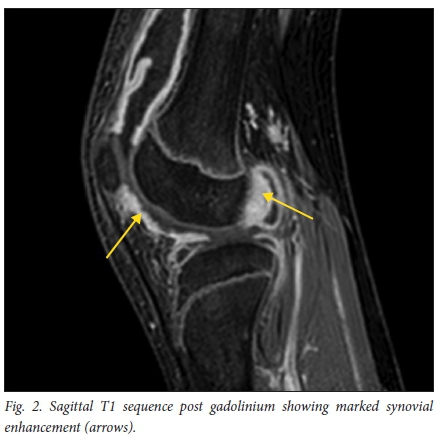

The MRI study was performed on a 1.5 Tesla Philips Intera MRI scanner. The scan showed a moderate joint effusion with extensive rice-body formation throughout all compartments of the knee joint (Fig. 1). This was evident as small rod-shaped areas of low signal on T1 and T2 sequences. Slightly larger pea-sized loose bodies were noted, mainly in the suprapatellar pouch. The post-contrast sequence also showed markedly enhancing synovium throughout the joint (Fig. 2), but no enhancement of the loose bodies. The articular cartilage appeared normal with no erosions or focal marrow oedema. Mildly prominent lymph nodes were noted in the popliteal fossa.